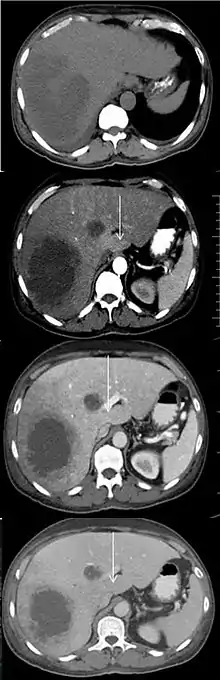

An abscess and a THAD (white arrow) on a contrast CT in native, arterial, portal and delayed phase.[1]